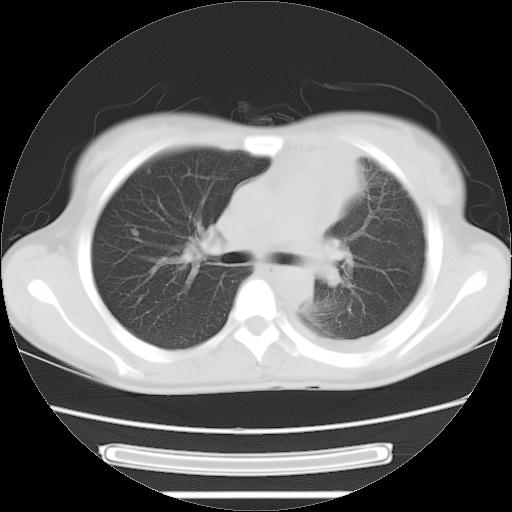

标题: CT21561:外院胸片提示胸腔积液,行CT检查。 [打印本页]

女,29岁,胸部不适,在外院胸片提示胸腔积液,到我院ct检查。

肺窗: